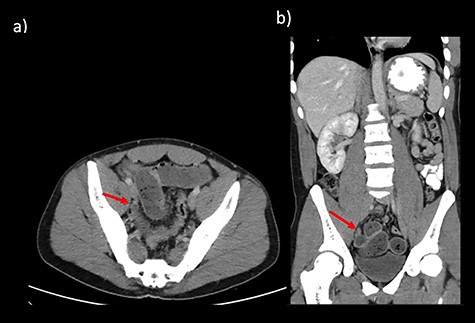

CT abdomen findings from Cases 1 and 2 showing distal SBO with the transition point in the pelvis. (a) Case 1 CT axial view. (b) Case 1 CT coronal view.

Case 2 is a 56-year-old male, with a virgin abdomen, who had 2 days of crampy abdominal pain, vomiting and obstipation. He was haemodynamically normal and afebrile. He had a distended abdomen with generalized tenderness. Blood tests showed an elevated lactate of 3 and WCC of 11.7 × 109. CT demonstrated distal SBO, with distension of small bowel up to 6 cm (Fig. 3). He underwent a diagnostic laparoscopy with an identification of MD at the transition point, subsequently exteriorized through a mini-laparotomy (Fig. 2). The apex of the MD was tethered to the mesentery through a band containing the diverticular blood supply. Small bowel resection and anastomosis was performed. Histopathology showed MD with acute inflammation, haemorrhage and necrosis, and no ectopic tissue.